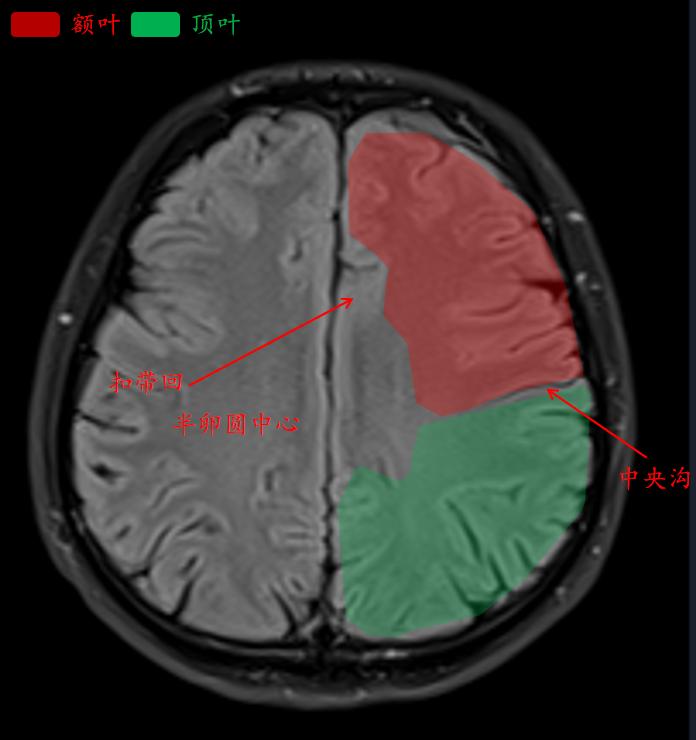

中央沟是额叶和顶叶的分界线。